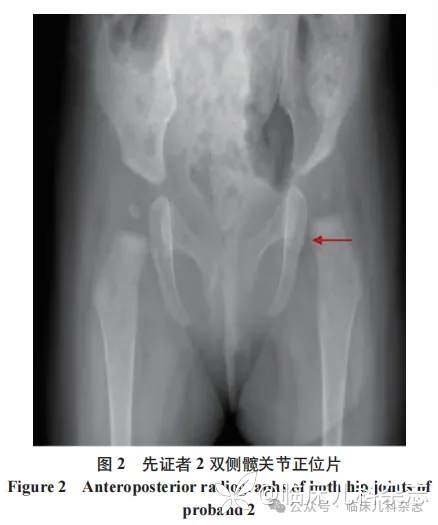

2023 年 2 月,患儿因「生长发育落后」就诊于本院门诊。体格检查 :体重 6.5 kg(<-2SD),身长 65 cm(<-1.5SD),头围 41.3 cm(<-1.5SD)。患儿一般状况可,精神好,头颅五官无特殊,心肺腹查体未见异常,生殖器发育正常。患儿四肢肌力弱,抬头 30 度,自主翻身不能,坐位前倾,前臂旋前,精细运动欠佳,拇指内收。腱反射正常,病理反射未引出,脑膜刺激征阴性。双侧髋关节 X 线正位片:双侧股骨头骨化中心发育不良,左侧髋关节 Shenton 线欠连续(图 2),头颅 MRI 未见明显异常。Gesell 发育量表:大运动 27 分,精细动作 20 分,适应性 27 分,语言 30 分,个人-社交 30 分,综合 26.8 分,落后于正常年龄 9 个月。家庭康复 2 个月后门诊复诊,患儿体重 7.3 kg(<-3SD),身长 67 cm(<-1.5SD),头围 42.0 cm(<-2SD),运动功能无进步(全身肌力弱,仍无法翻身、独坐,俯卧位支撑弱),关节问题加重(左下肢短缩、扶立位足外旋),右侧拇指持续内收影响精细动作。之后患儿失访。